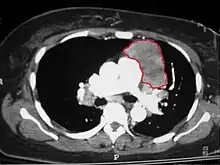

When a thymoma is suspected, a CT/CAT scan is generally performed to estimate the size and extent of the tumor, and the lesion is sampled with a CT-guided needle biopsy. Increased vascular enhancement on CT scans can be indicative of malignancy, as can be pleural deposits.[2] Limited biopsies are associated with a very small risk of pneumomediastinum or mediastinitis and an even-lower risk of damaging the heart or large blood vessels. Sometimes thymoma metastasize for instance to the abdomen.[6]

The diagnosis is made via histologic examination by a pathologist, after obtaining a tissue sample of the mass. Final tumor classification and staging is accomplished pathologically after formal surgical removal of the thymic tumor.